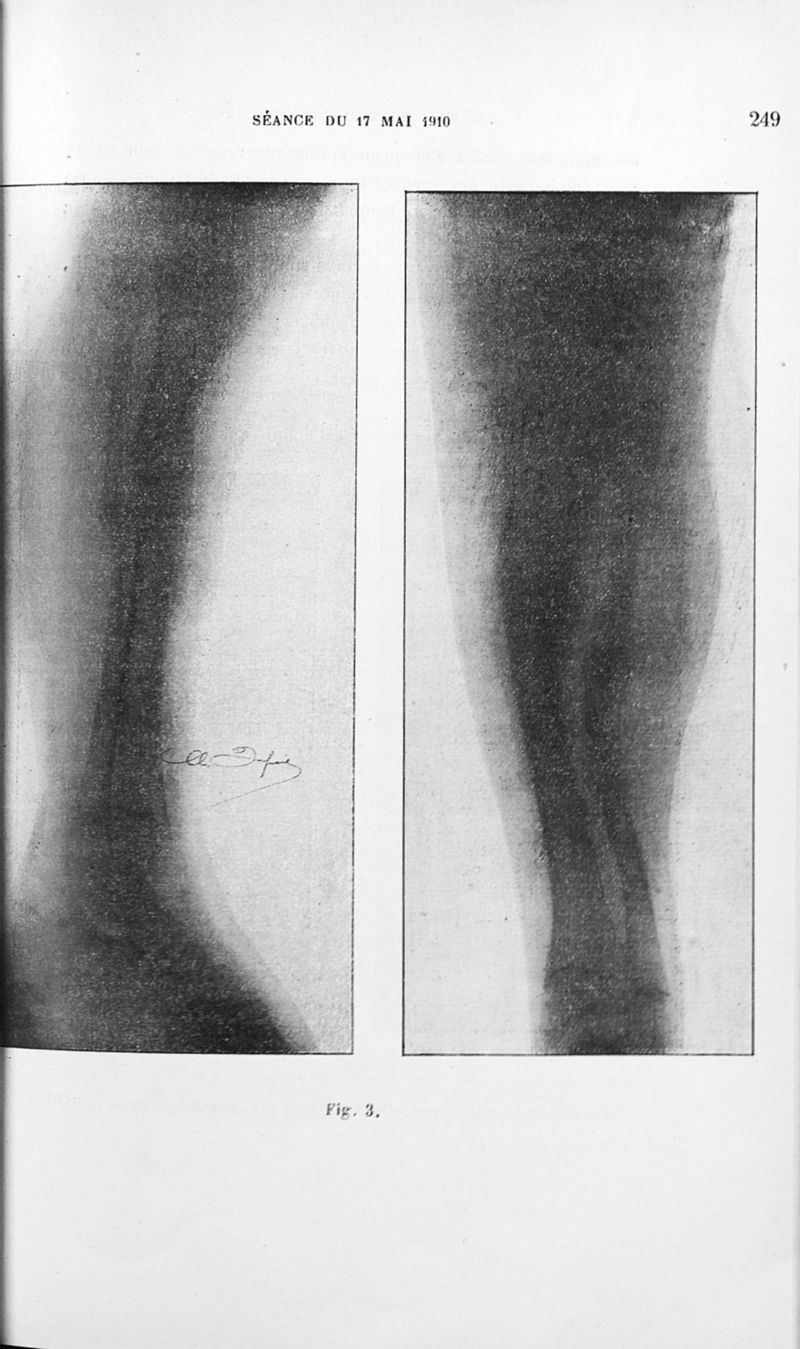

Bulletins de la société de pédiatrie de Paris

Tome douzième. - Paris : G. Steinheil, 1910.